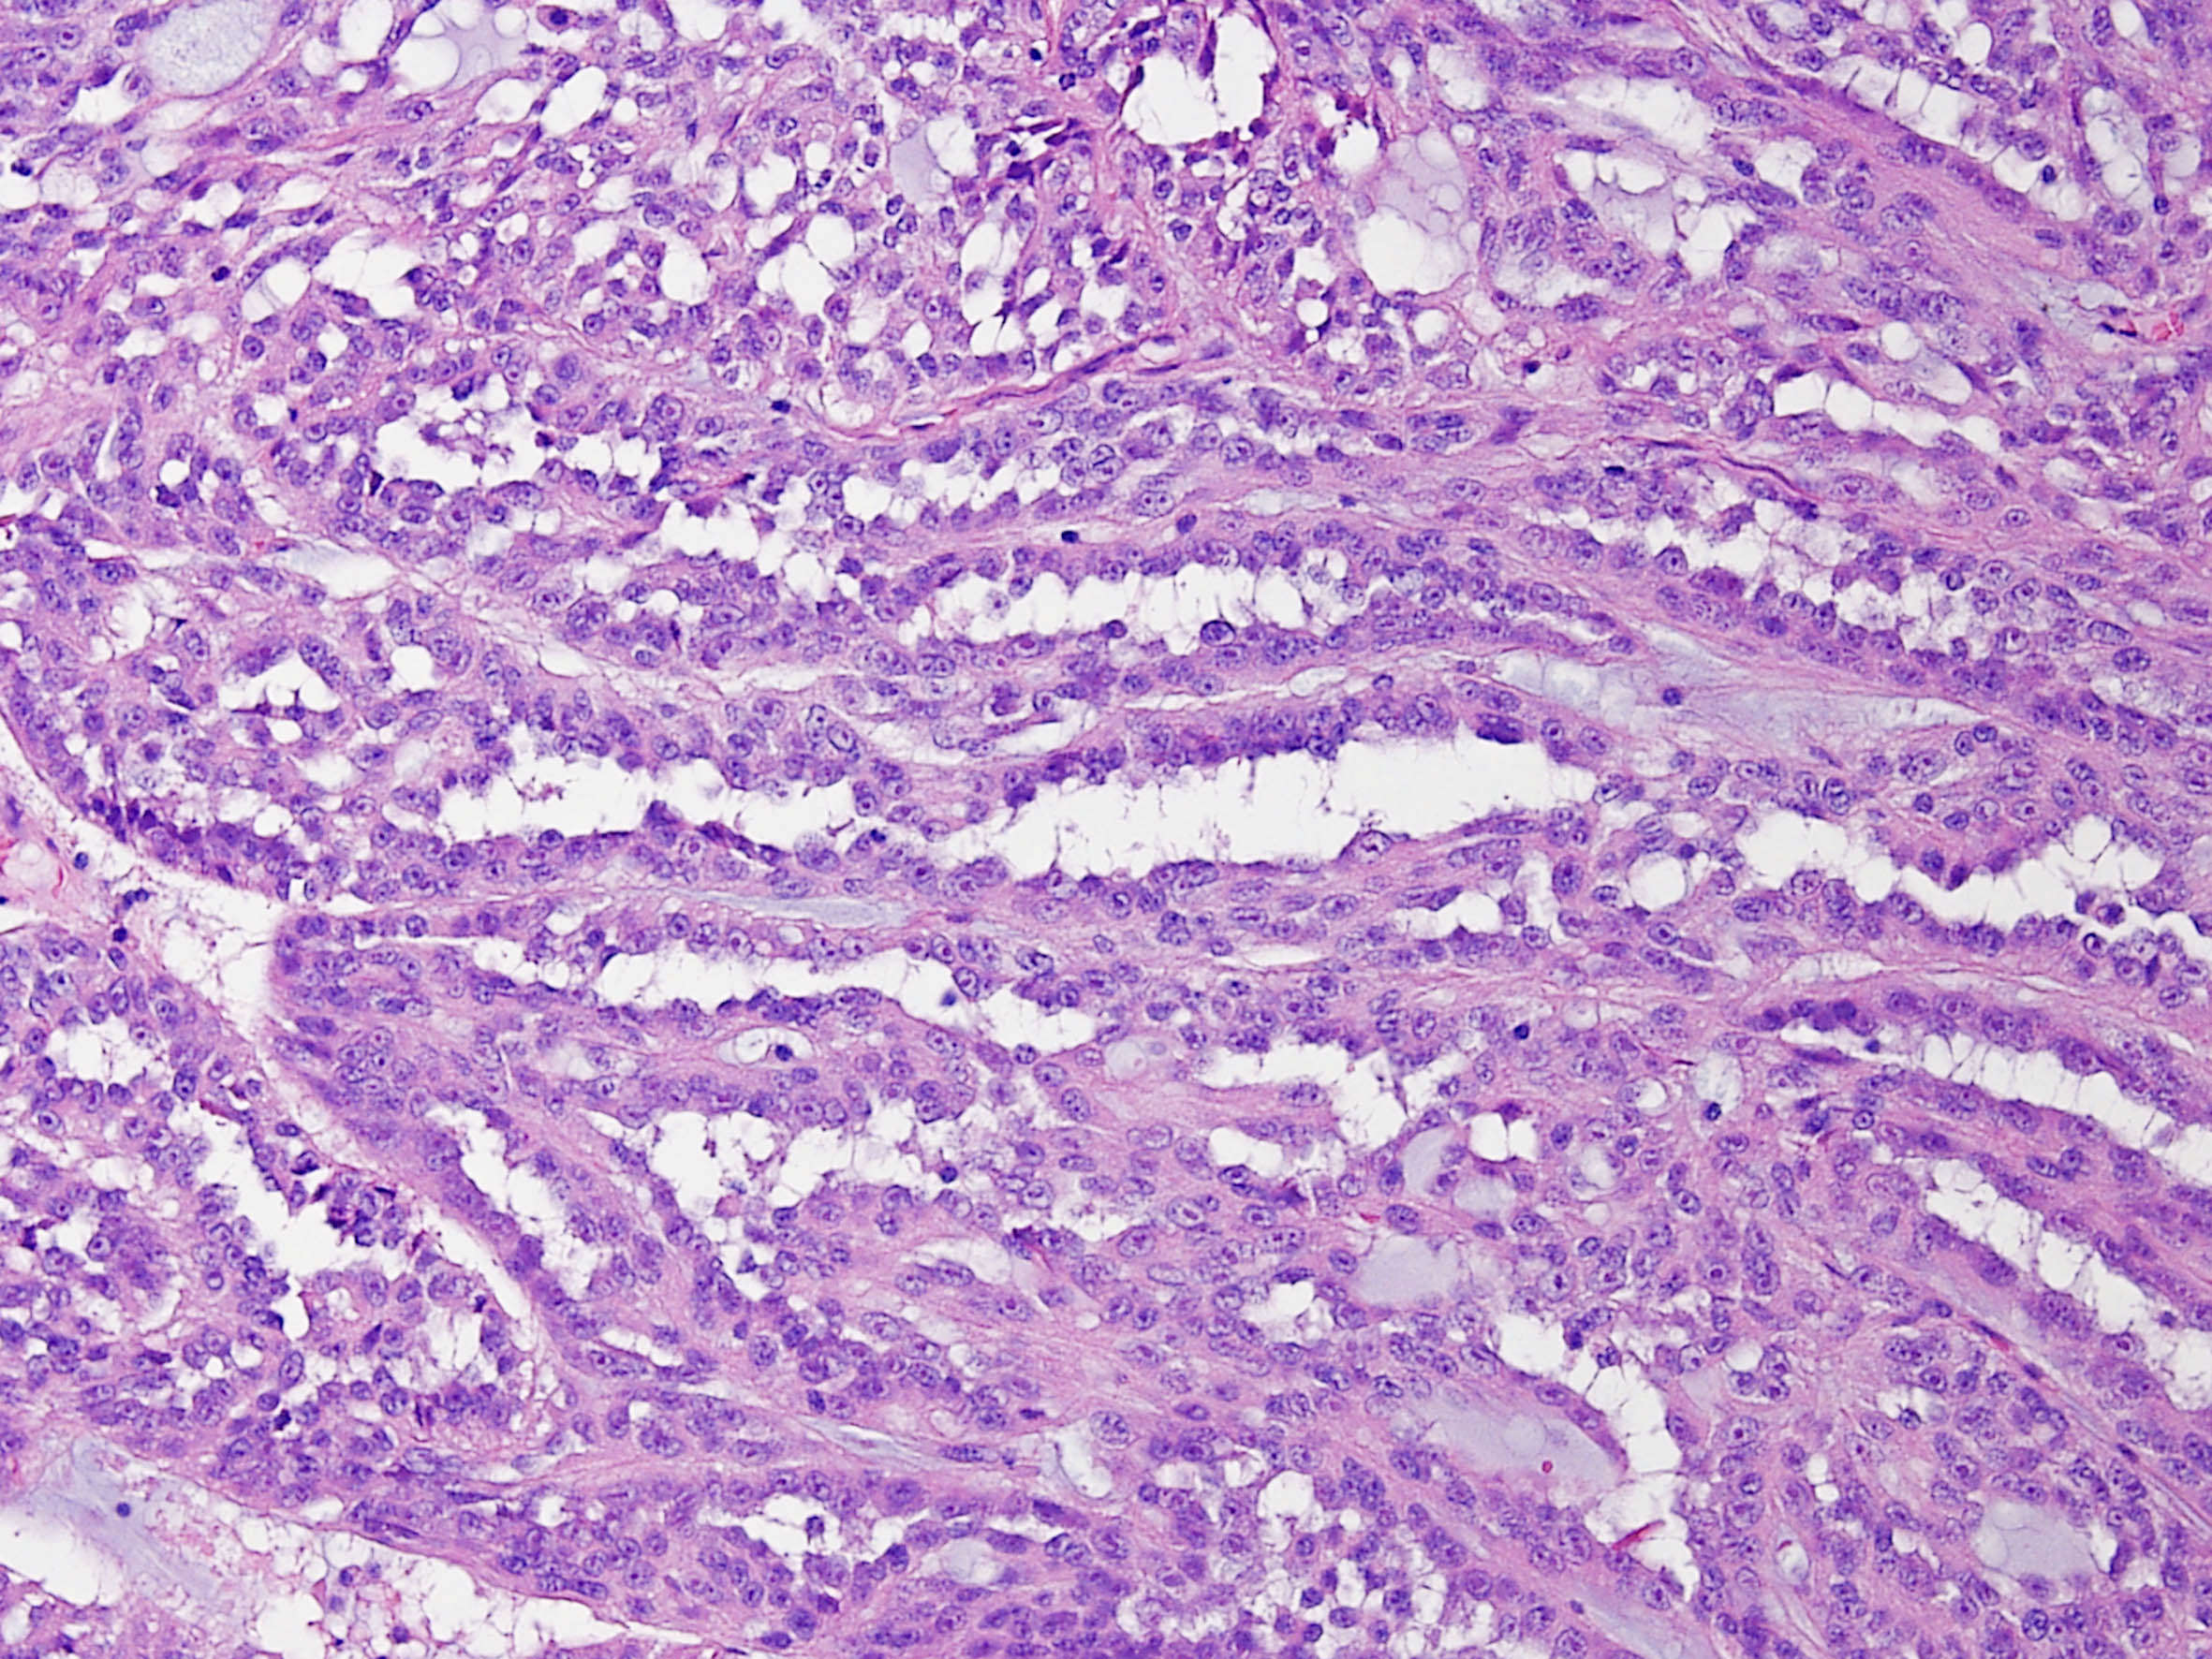

Classification of renal tumors

Case ID: 171